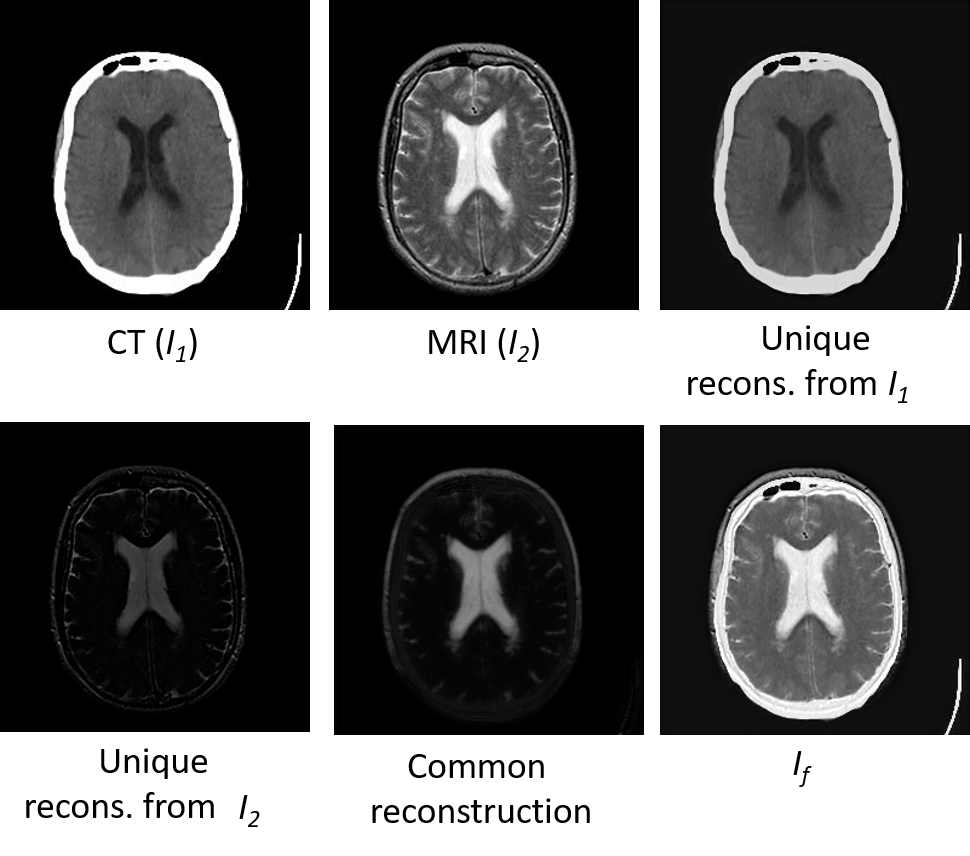

In FNet, we first estimate the unique and common features. Then these features undergo convolution operations to obtain the unique and common reconstruction parts, which are then added to get the fused image. Fig. 9 shows the unique and common reconstructions of the CT-MRI image fusion task on the Harvard medical dataset. As we can see, the unique reconstruction from the CT image () preserves the anatomical information, whereas the unique part of the MRI image () has the tissue details. The common reconstruction part consists of the shapes that are present in both the images. The fused image consists of the unique and common reconstruction parts. More visualization of intermediate results are given in the supplementary material.